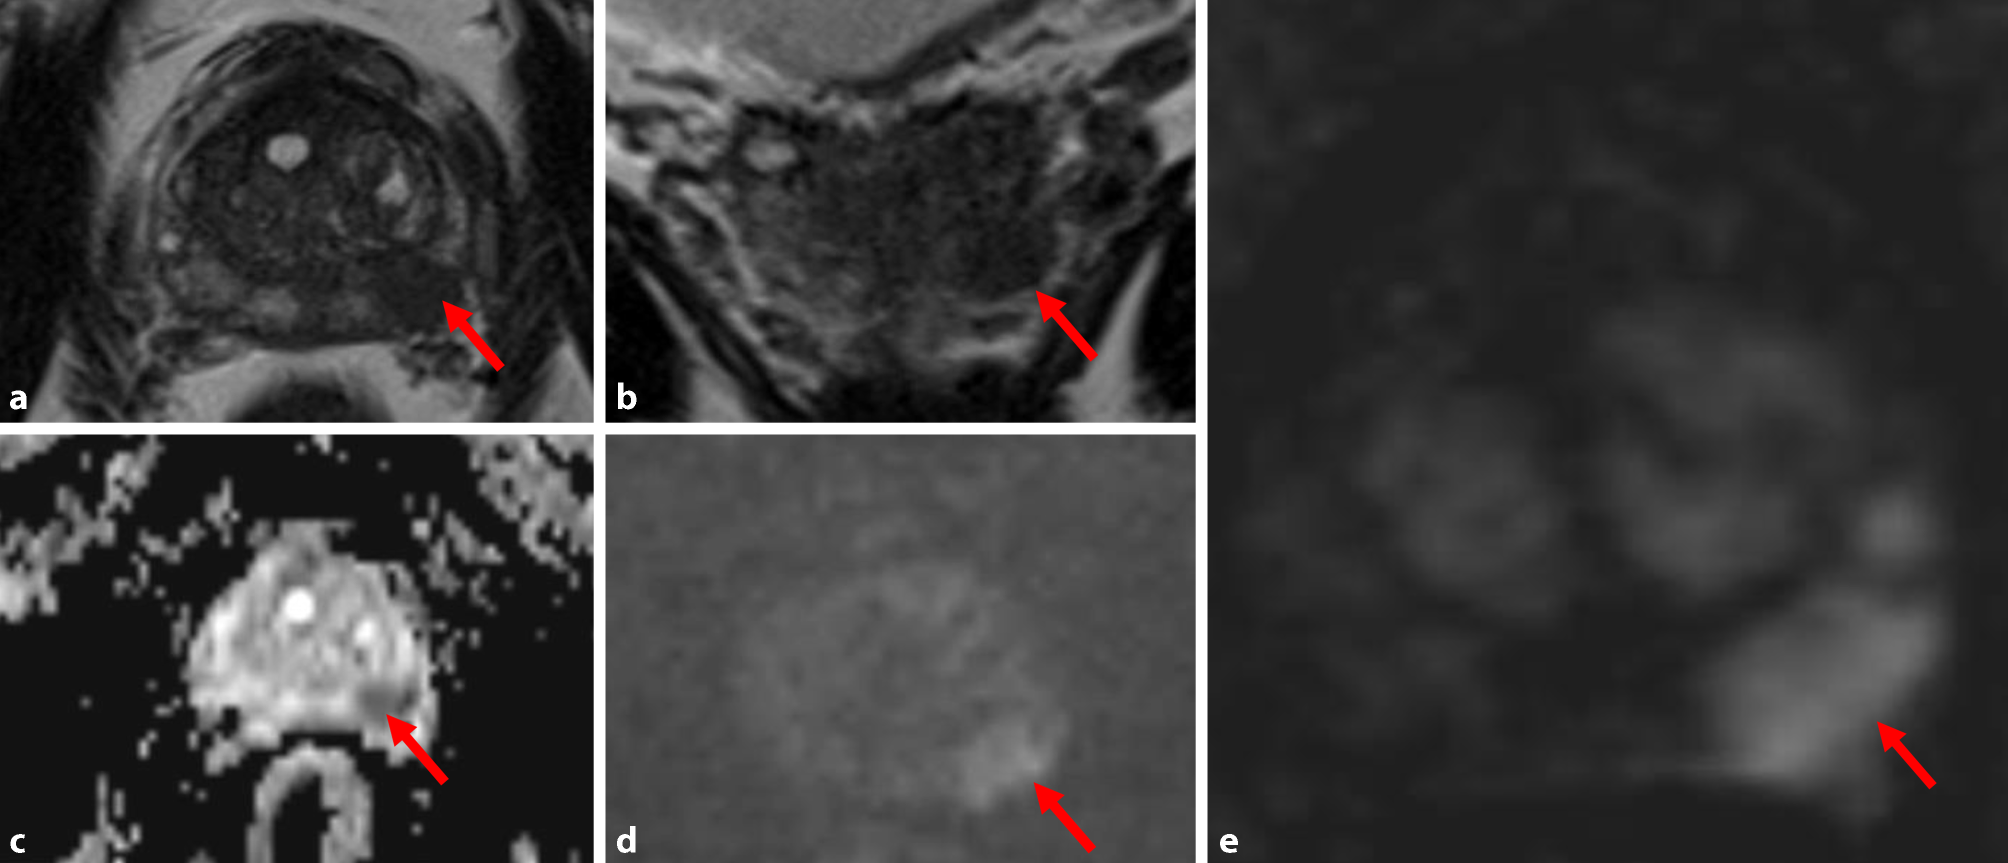

Fig. 1

Prostate carcinoma in the peripheral zone (red arrow): hypointensity on axial T2-weighted (a) and on follow-up T2-weighted images (b); hypointensity on ADC (Apparent Diffusion Coefficient) maps (c) and hyperintensity on diffusion-weighted images (d); marked early contrast enhancement on dynamic contrast-enhanced sequences (e)

In recent years, prostate MRI is increasingly used to visualize PCa [7]. A new, simplified version, PI-RADS v2 was introduced in 2012 [8]. PI-RADS v2, too, is based on multiplanar T2-weighted sequences (T2w), diffusion-weighted sequences (DWI), and dynamic contrast-enhanced sequences (DCE). The prostatic anatomy is evaluated in the T2w sequences. The prostatic zones can be discriminated and important extraprostatic structures, such as the neurovascular bundles, can be seen. DWI is the key sequence in the PI-RADS system. PCa has a higher cell density than the surrounding normal prostatic tissue. Hence, the Brownian motion within the tumor is limited. This diffusion restriction can be visualized with DWI, but the spatial resolution of DWI is low. Intravenous contrast agent, usually gadolinium, has to be administered for the DCE sequences. DCE shows the contrast enhancement of the prostate over the time. PCa is believed to have an early gadolinium uptake and an early wash-out of the contrast agent. In the currently used PI-RADS v2, DCE plays a minor role. An early contrast enhancement in the DCE can lead to an upgrading from PI-RADS 3 to PI-RADS 4. Combining the aforementioned different sequences in one MRI examination has become known as multiparametric MRI (mpMRI; Fig. 1). MpMRI is well evaluated, but it has several drawbacks. To overcome some of them, a number of groups have proposed a “biparametric prostate MRI” (bpMRI).